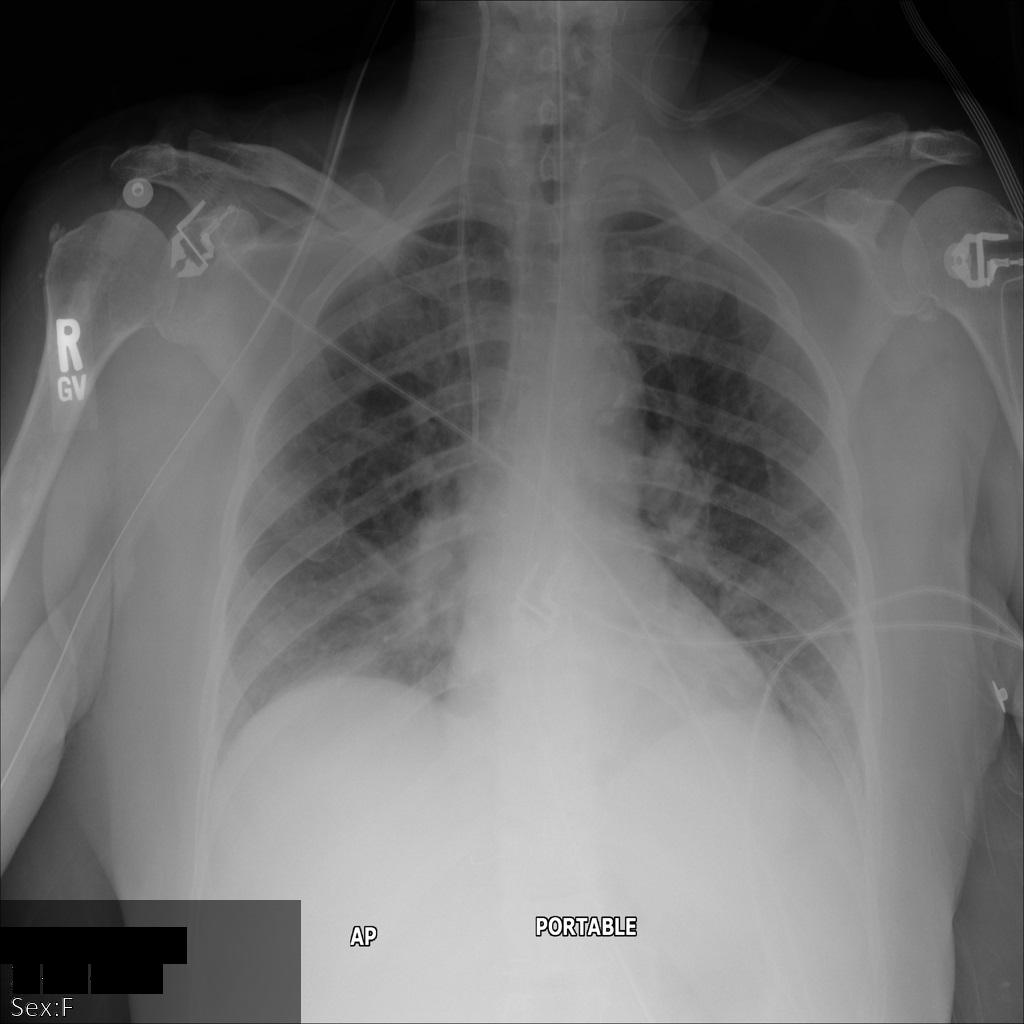

下图显示了未经遮盖的患者 X 光片:

xray2_unredacted

使用 REDACT_SENSITIVE_TEXT 选项将图片提交到 Cloud Healthcare API 后,图片显示如下:

xray2_redact_sensitive_text

您可以看到以下情况:

• 图片左下方的 PERSON_NAME 已被遮盖

• 图片左下方的 DATE 已被遮盖

根据默认 DICOM infoType,该患者的性别不属于敏感文本,因此未遮盖。